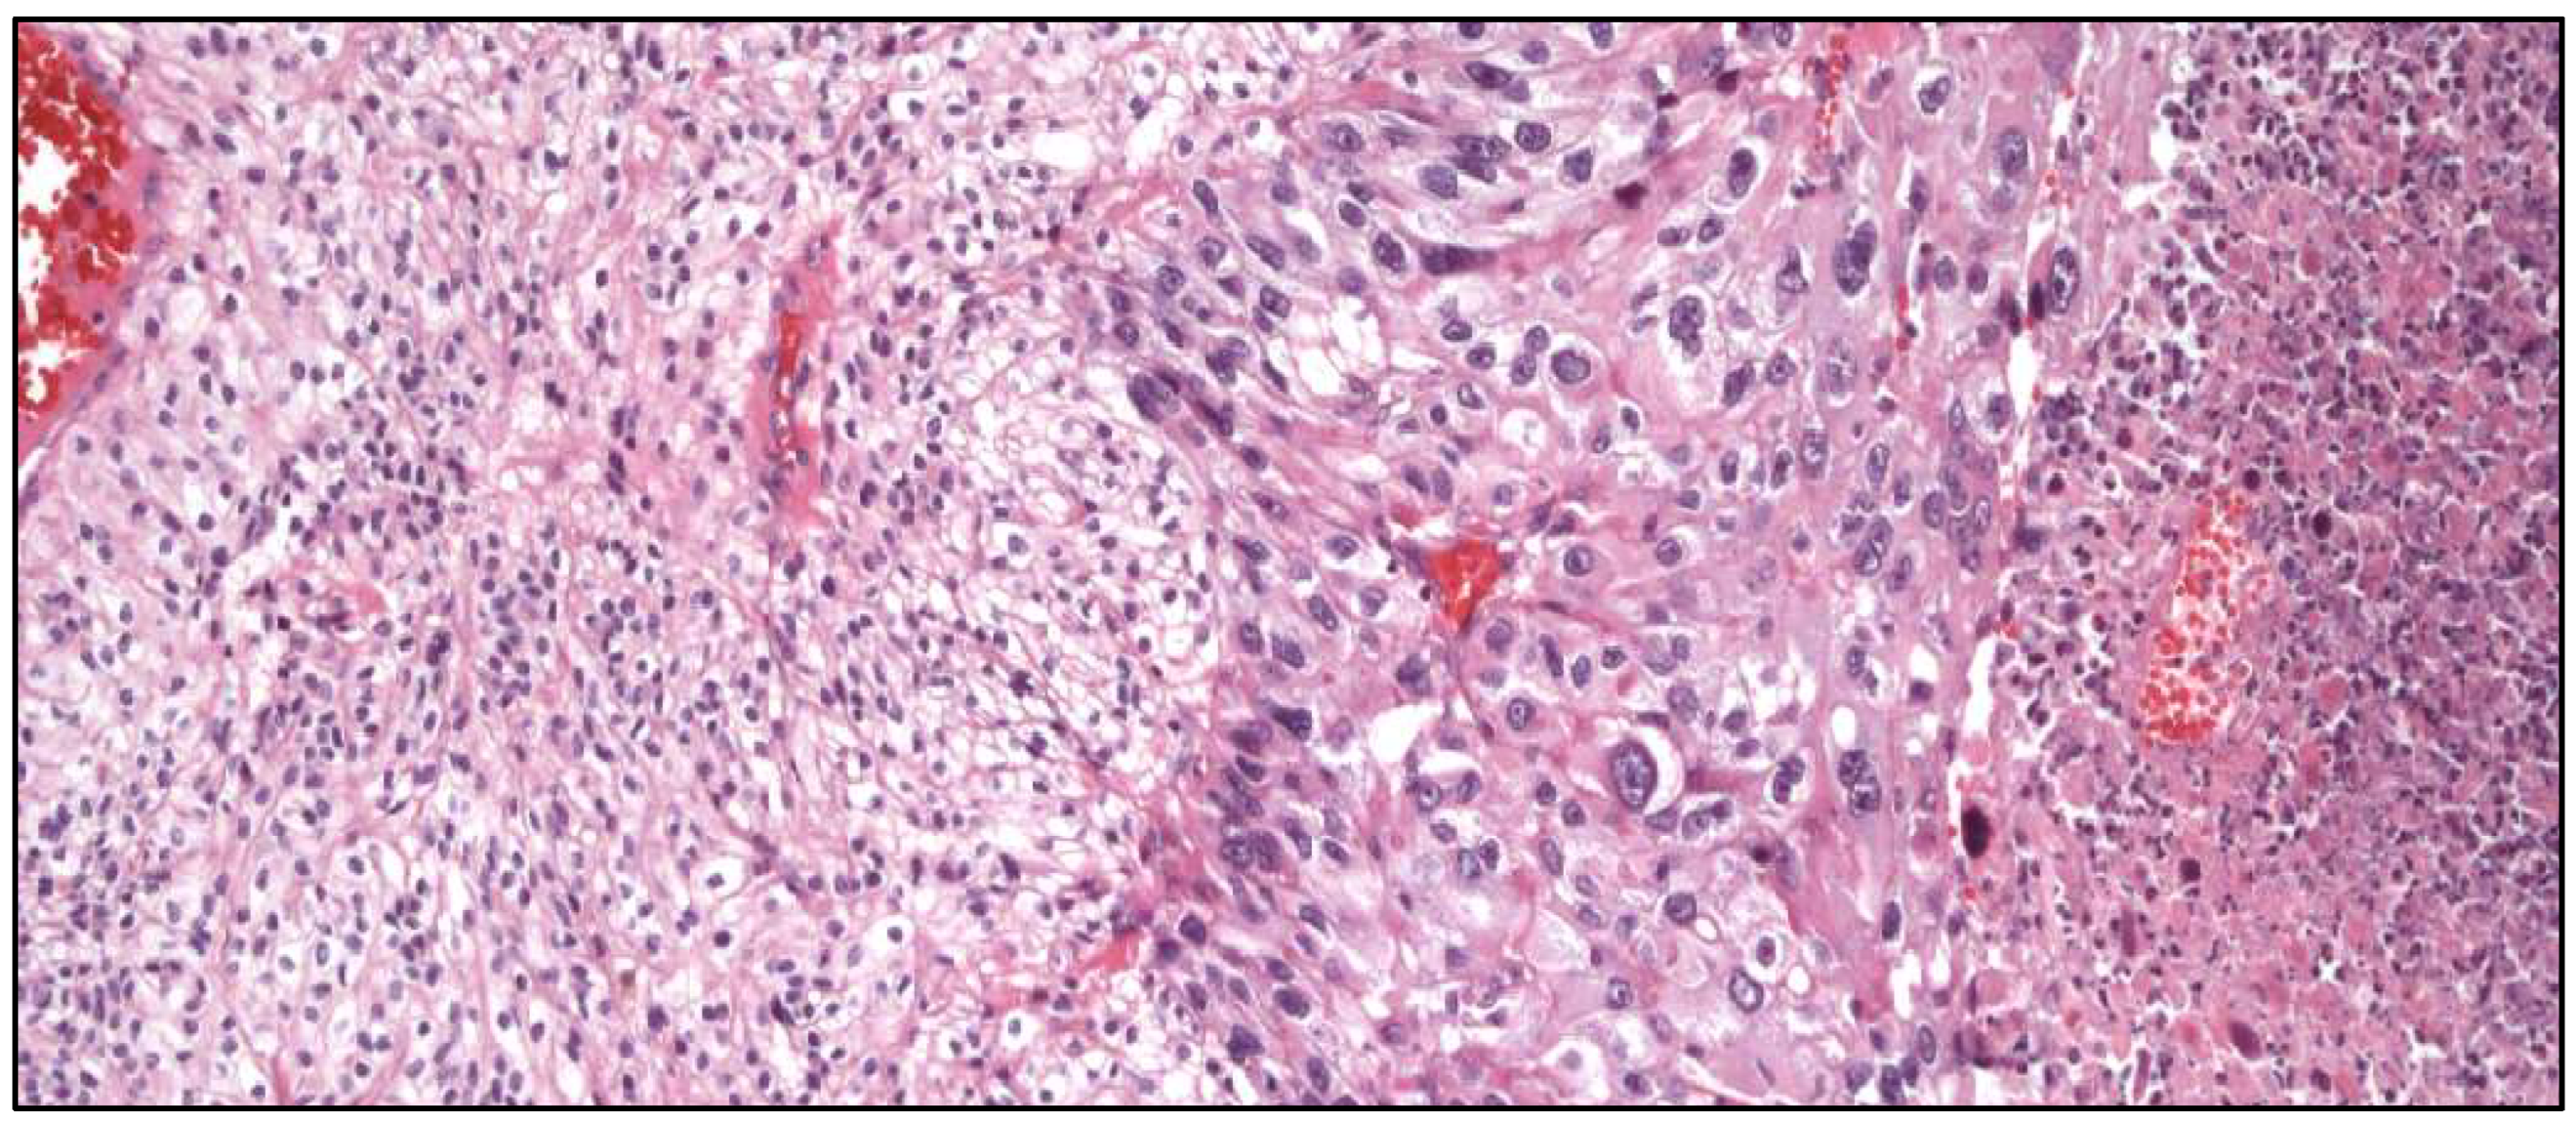

- “Warty” PeCa (Figure 5).

- Basaloid PeCa.

- Clear cell squamous PeCa.

- Lymphoepithelioma-like PeCa.